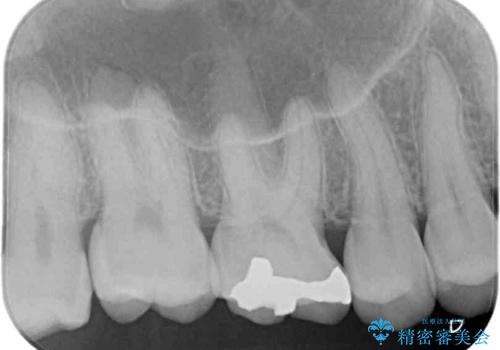

まず麻酔をして銀歯を外し、むし歯を除去し、形を整えて型取りします。

そして次の来院時、セラミックインレーを装着し、噛み合わせなどの調整を行います。

インレーを装着するときは、唾液や血液による接着力の低下を避けるためにラバーダム防湿を行いました。